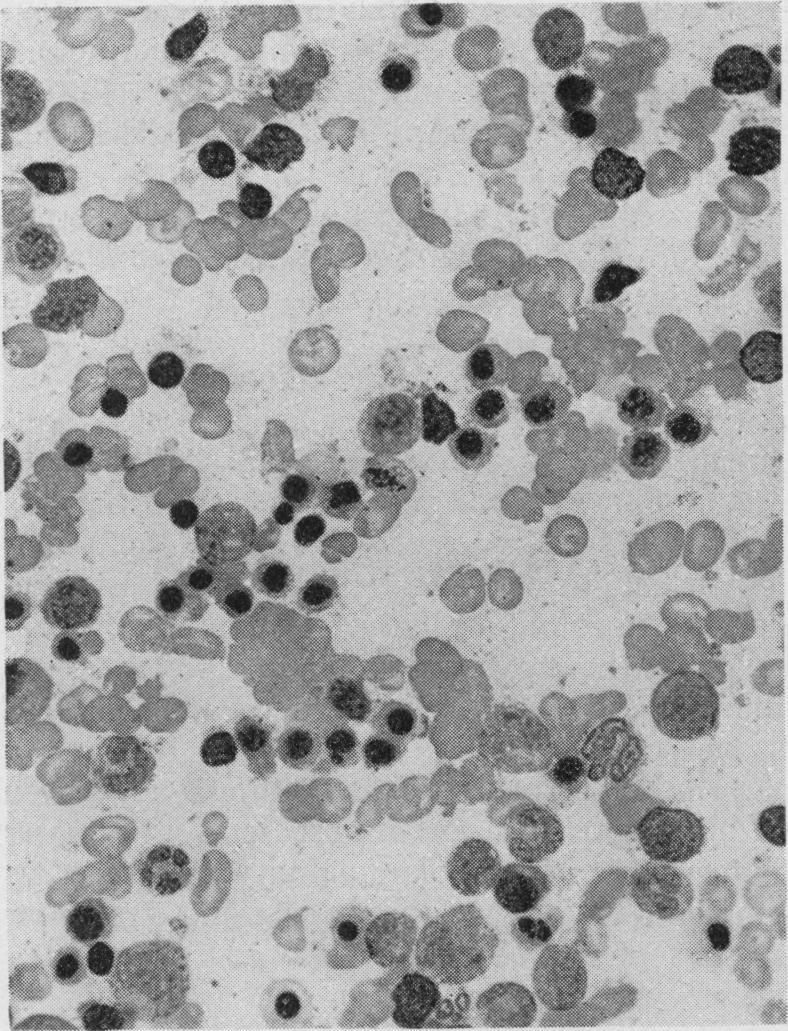

STUDIES OF FOLATE DEFICIENCY IN MAN.

Proc R Soc Med. 1964 May;57(5):377-84. doi: 10.1177/003591576405700516.